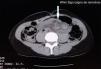

Se presenta el caso de un paciente femenino de 33 años, la cual ingresó a urgencias por dolor y distensión abdominal, además de ausencia de evacuaciones de 2 días de evolución. Se realizó TAC abdominal en la que se diagnosticó vólvulo de sigmoides (fig. 1), apreciando signo de remolino (fig. 1). Mediante rectosigmoidoscopia, se logra su resolución y la paciente es egresada. Tres semanas después acude nuevamente por presentar dolor abdominal súbito, distensión y vómito fecaloide, así como deshidratación de 2 días de evolución. Durante la exploración física se encontró ausencia de peristalsis, dolor abdominal y timpanismo generalizado, signo de von Blumberg positivo. Su BH reportó leucocitosis de 17.3 con un 16% de bandas. No se contó con radiografías. Se realizó ultrasonido abdominal con hallazgo de distensión generalizada de asas intestinales y presencia de líquido libre. Por lo anterior se decidió realizar laparotomía exploradora, considerando el diagnóstico de vólvulo sigmoideo recurrente, por el antecedente mencionado. Inesperadamente se encontró vólvulo simultáneo de intestino delgado y de sigmoides (fig 2). La porción afectada del intestino delgado fue el íleon, en aproximadamente 2.7m justo a 5cm antes de la válvula ileocecal, la cual presentaba necrosis por torsión de su mesenterio en sentido horario, junto al sigmoides que a su vez también estaba volvulado en el mismo sentido, por lo que se decidió realizar resección ileal con anastomosis primaria y resección de sigmoides con procedimiento de Hartmann.

Además, en la TAC, existe el denominado signo de remolino (whirl sign), descrito por Fisher para vólvulo de intestino medio, como una imagen producida cuando asas intestinales y sus vasos giran alrededor de un punto de obstrucción creando un «remolino» en los tejidos blandos dentro de grasa mesentérica atenuada6,7. Este signo y la desviación medial del ciego y colon descendente son de utilidad diagnóstica en el vólvulo doble8.